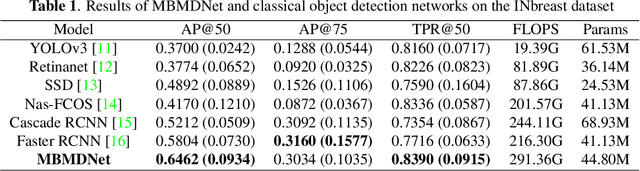

Multi-Head Feature Pyramid Networks for Breast Mass Detection

Feb 22, 2023

Analysis of X-ray images is one of the main tools to diagnose breast cancer. The ability to quickly and accurately detect the location of masses from the huge amount of image data is the key to reducing the morbidity and mortality of breast cancer. Currently, the main factor limiting the accuracy of breast mass detection is the unequal focus on the mass boxes, leading the network to focus too much on larger masses at the expense of smaller ones. In the paper, we propose the multi-head feature pyramid module (MHFPN) to solve the problem of unbalanced focus of target boxes during feature map fusion and design a multi-head breast mass detection network (MBMDnet). Experimental studies show that, comparing to the SOTA detection baselines, our method improves by 6.58% (in AP@50) and 5.4% (in TPR@50) on the commonly used INbreast dataset, while about 6-8% improvements (in AP@20) are also observed on the public MIAS and BCS-DBT datasets.